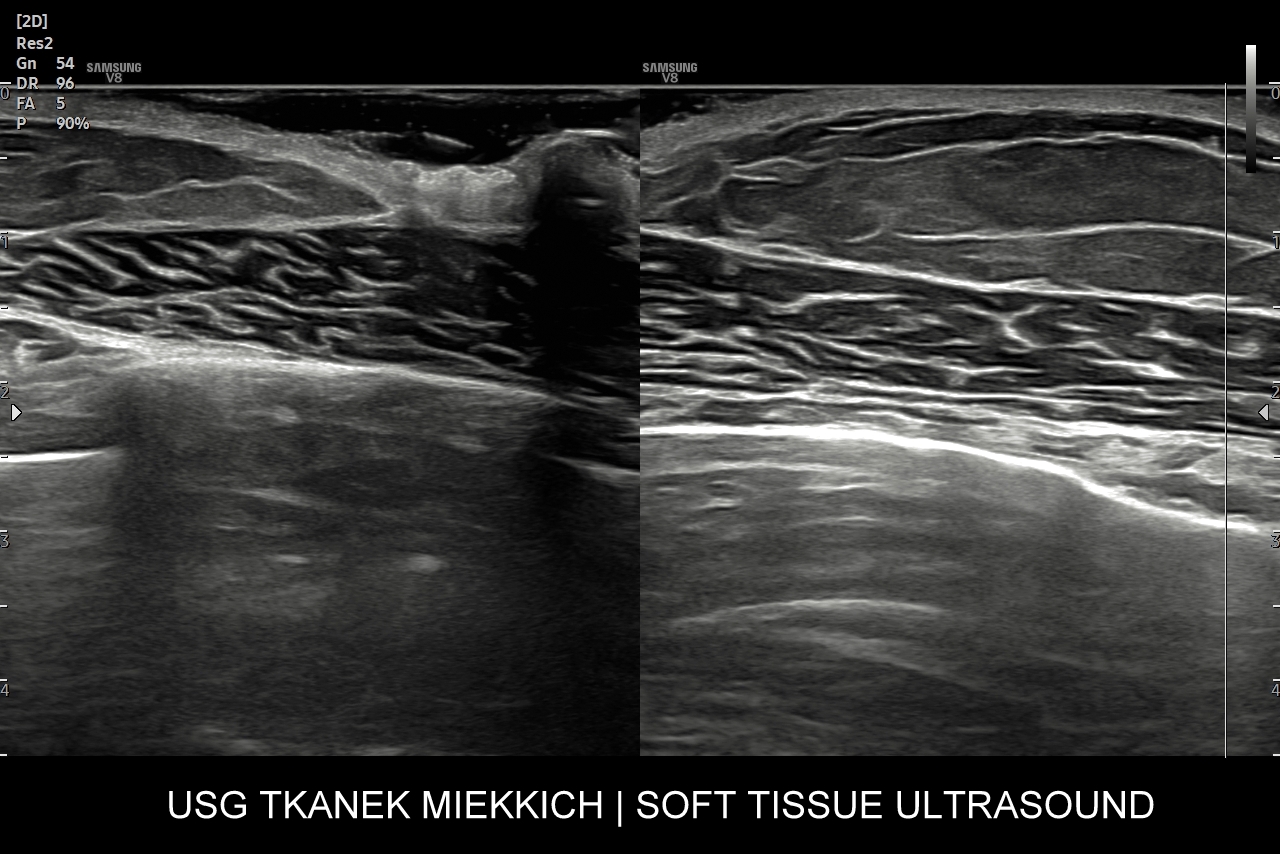

USG tkanek miękkich

USG tkanek miękkich obejmuje ocenę diagnostyczną opisanych już wcześniej patologii, ale także zmian miękkotkankowych położonych w głębszych warstwach powłok oraz obszarach podpowięziowych takich jak chrząstki, ciała tłuszczowe, mięśnie, ścięgna, troczki, pochewki ścięgniste, stawy i gangliony, torbiele wrodzone, czy aparat paznokciowy.

Niektóre patologie miękkotkankowe mają predylekcję do występowania w określonych obszarach ciała. Przykładowo w obrębie szyi spotyka się torbiele boczne, torbiele centralne szyi oraz inne pozostałości po embrionalnych łukach skrzelowych. Na karku, szyi oraz w pachwinach badanie USG wykorzystywane jest często przy ocenie i różnicowaniu węzłów chłonnych, które mogą ulegać powiększeniu w przebiegu chorób nowotworowych, rozrostowych, jak i infekcyjnych (np. przeziębienie, choroba kociego pazura). Z kolei na plecach i skórze głowy dość często lokalizują się kaszaki, a na dłoniach i stopach włókniaki rozścięgien.

Ważną grupą dermatoz, w których diagnostyce ogromną rolę odgrywa badanie USG skóry jest tzw. tetrada związana z patologią wywodzącą się z okluzji mieszków włosowych, tj. torbiel pilonidalna lokalizująca się szparze międzypośladkowej; trądzik odwrócony (ang. hidradenitis suppurativa)  lokalizujący się w pachwinach i pod pachami; trądzik skupiony (ang. acne conglobata) lokalizujący się na twarzy, ramionach i plecach oraz dissecting cellulitis, rzadkie i ciężkie schorzenie lokalizujące się na owłosionej skórze głowy.